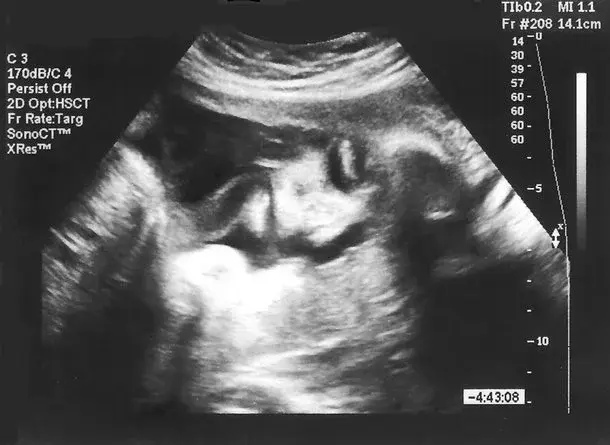

Wyróżnia się aż trzy trymestry ciąży, a w pierwszym z nich mamy do czynienia z następującymi wydarzeniami w brzuszku mamy:

Zapłodnienie i implantacja zarodka Po zapłodnieniu embrion rozwija się niezwykle szybko. W pierwszym trymestrze ciąży obserwuje się najbardziej wzmożoną „pracę” wykonywaną przez dziecko w przeciągu całej ciąży. Po zapłodnieniu musi dojść jeszcze do implantacji zarodka w ścianie macicy. Dochodzi do niej po około 10-12 dniach od dnia spodziewanej owulacji. Może to zostać zauważone przez przyszłą mamę przez pojawienie się niewielkiego krwawienia, jednak zazwyczaj mija bezobjawowo. 5 tydzień ciąży Embrion składa się już z trzech listków zarodkowych: ektodermy, mezodermy i endodermy, z których rozwiną się poszczególne narządy.Reklama